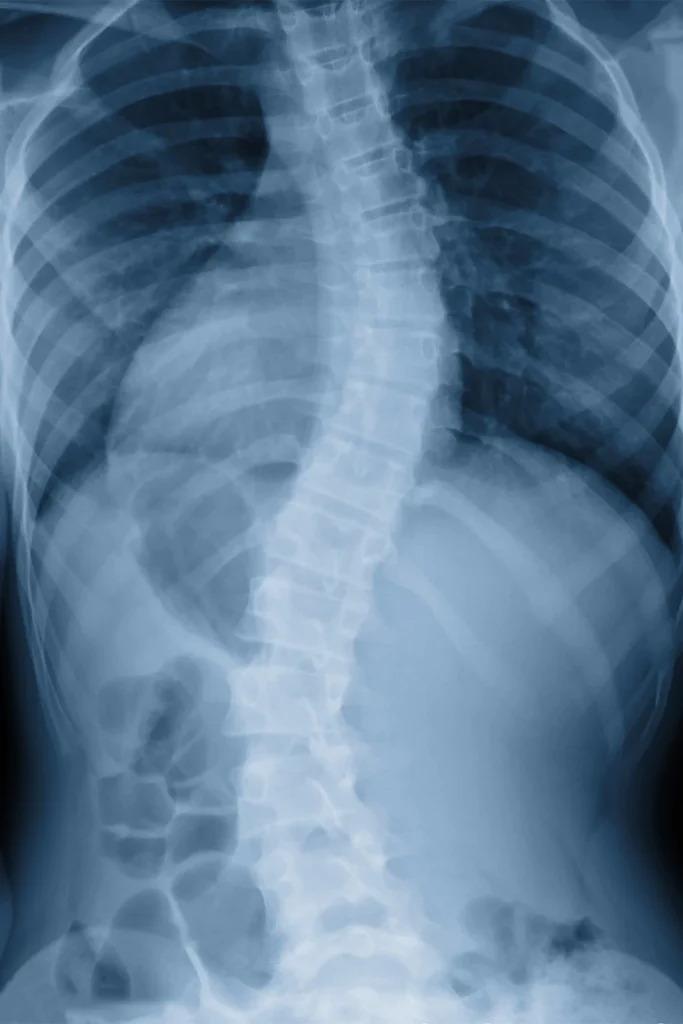

A disc herniation or bulge occurs when one of the spinal discs — the soft, cushion-like structures between your vertebrae — becomes compressed or damaged, often pressing on nearby nerves. This can cause localized pain as well as numbness, tingling, or weakness that radiates into the arms or legs.

We begin with a thorough evaluation, which may include digital X-rays to assess disc position and spinal alignment. Treatment typically includes gentle chiropractic adjustments, spinal decompression therapy, and targeted mobility work. These techniques help reduce inflammation, relieve pressure on the disc, and create space for healing.

When the spine is out of alignment or under stress, it can compress the discs and irritate surrounding nerves. Chiropractic care works by correcting the underlying structural issues, reducing pressure on the affected area, and restoring healthy movement. Many patients experience noticeable relief without the need for injections or surgery.